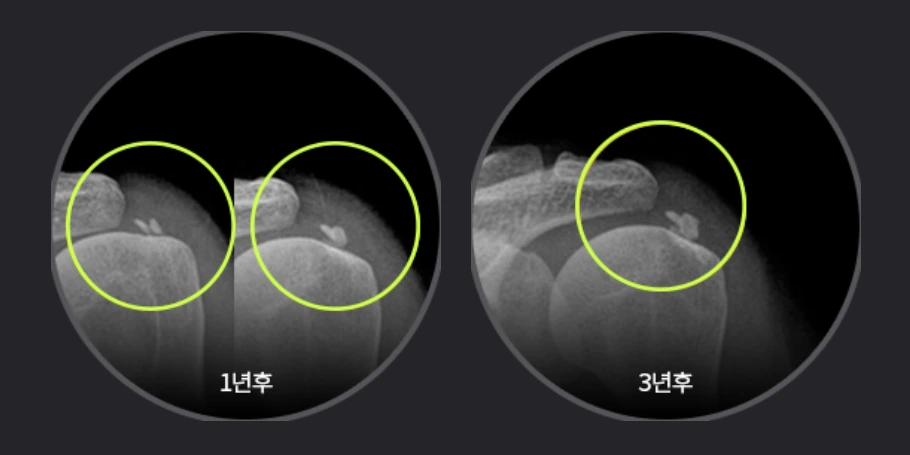

“어깨관절염 치료로는 초기에는 비수술적치료를 우선 적용하지만 증상이 심해지면 관절내시경으로 파열된 힘줄을 봉합해 염증을 없애는 수술이나 심한 관절염이 발생한 어깨관절을 인공관절로 교체하는 인공관절 치환술을 고려해야 합니다”라고 김학수 원장님이 알려주시네요.

캡처.PNG